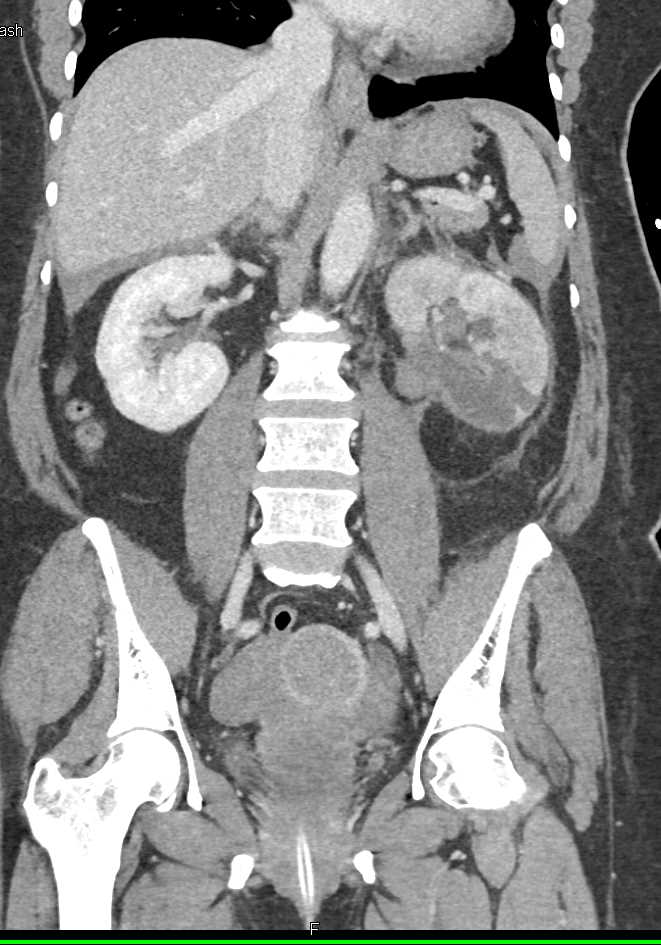

Acute Pyelonephritis Right Kidney